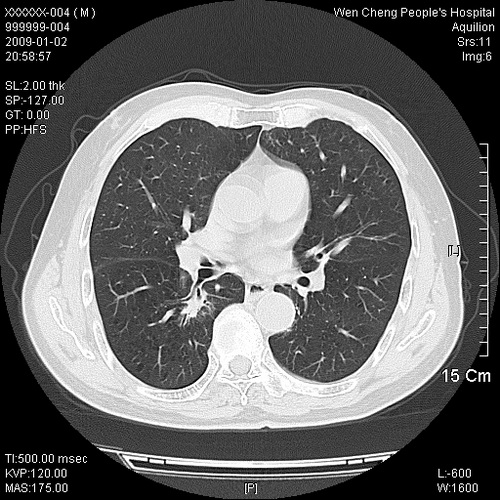

男性,73岁,有慢支病史,肿瘤系列标志物检验正常,血沉及血常规正常

右肺下叶背段小片状 磨玻璃样模糊影,内见血管及含气支气管像,支气管管壁增厚。考虑:慢性炎症!

右肺下叶背段小片状 实性与磨玻璃样影,内见血管及含气支气管像,支气管管壁增厚,边缘见长毛刺影。考虑:慢性炎症或肿瘤!建议抗炎治疗复查,密切观察随访!

右肺下叶片团状影内见扩张的含气支气管和支气管管壁增厚,其周有磨玻璃样模糊影和长毛刺。考虑慢性炎症可能性大。

2、右肺下叶片团状影内见扩张的含气支气管和支气管管壁增厚,其周有磨玻璃样模糊影和长毛刺。考虑周围型肺ca可能,结核不排。

高度提示细支气管肺泡癌,建议抗炎治疗半月观察病灶变化,如无明显改变,建议立即手术治疗.